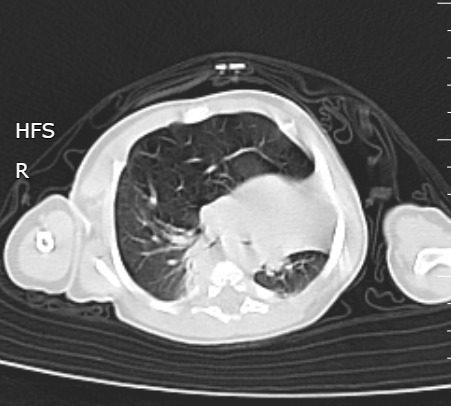

Un nouveau-né âgé de 1 mois est admis aux urgences pédiatriques pour prise en charge d’une détresse respiratoire. Le début de la symptomatologie remonte à la naissance, par l’installation d’une polypnée s’aggravant lors des cris et de l’alimentation, associée à des épisodes de toux sèche. L’examen clinique trouve un nouveau-né tachypnéique, cyanosé avec tirage intercostal et bombement de l’hémithorax droit associé à un wheezing auscultatoire et une SaO2 à 90 % à l’air ambiant. Le patient est mis sous oxygénothérapie et une radiographie thoracique est réalisée, objectivant une hyperaération de l’hémichamp pulmonaire droit refoulant le médiastin (fig. 1). Un scanner est effectué sans injection de produit de contraste et sans sédation, montrant une hyperclarté hypovasculaire avec une expansion du lobe supérieur gauche, refoulant le médiastin et la trachée à gauche, associée à une atélectasie du lobe inférieur droit et de l’hémichamp pulmonaire controlatéral (fig. 2). L’ensemble des éléments radio-cliniques plaident en faveur d’un emphysème lobaire géant compressif congénital (ELGC). Une lobectomie supérieure droite est réalisée, avec une bonne évolution clinique.

Le scanner est plus utile pour analyser l’emphysème, en montrant un lobe distendu, hyperclair, avec une raréfaction vasculaire. Les autres lobes sont beaucoup plus denses, car faiblement aérés et collabés. En cas de volumineux emphysème, il existe souvent une hernie rétrosternale du lobe atteint vers le côté opposé. La tomodensitométrie (TDM) joue un rôle fondamental pour éliminer un emphysème obstructif secondaire à une compression extrinsèque de la bronche par une masse médiastinale, plus exceptionnellement, secondaire à une lésion bronchique endoluminale.6